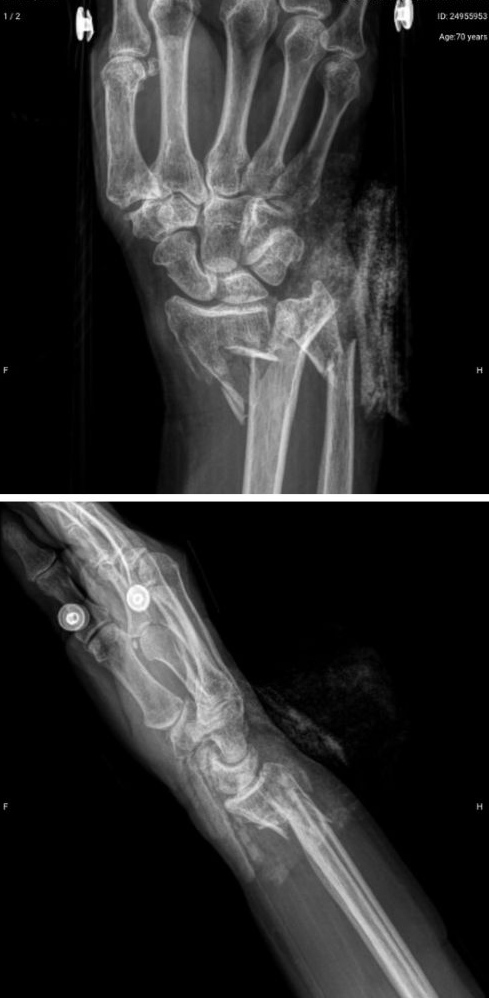

Antes

Después